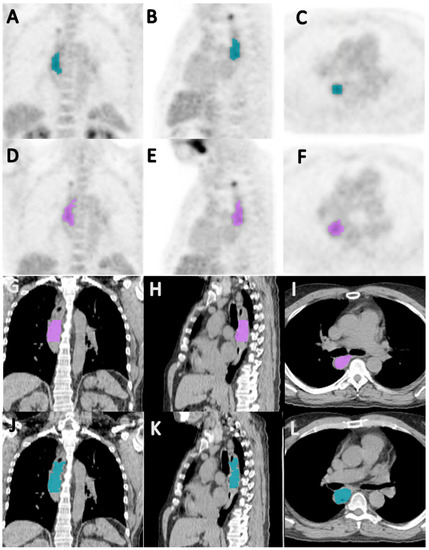

Figure 2. Coronal (A,D), sagittal (B,E), and axial (C,F) PET images, and coronal (G,J), sagittal (H,K), and axial (I,F) CT images showing segmentation of primary tumor by reader 1 (AC,GI) and reader 2 (DF,JL), in a 64-year-old male patient with esophageal squamous cell carcinoma; the Jaccard index and a dice similarity coefficient for inter-reader agreement on the segmented volumes were 0.657 and 0.793, respectively.

Baseline PET/CTs were segmented in 86 patients (58 men, 28 women) with a mean age of 65 years (range, 41–87). A total of 12 patients were excluded from the analysis due to small lesion size (<50 pixels), leaving a maximum of 74 patients for analysis. The clinical outcomes were dichotomized and the patients whose clinical outcomes were not known were excluded from respective assessments. Although there were several chemotherapy combinations, virtually all were platinum-based and nearly 92% of the patients received either platinum/paclitaxel- or platinum/irinotecan-based chemotherapy. Patient characteristics are presented in Table 2. There was good to excellent inter-reader agreement with the average Jaccard indices for the CT and PET data being 0.64 and 0.75, respectively, and the average dice similarity coefficients for the CT and PET data being 0.77 and 0.85, respectively (Figure 2).